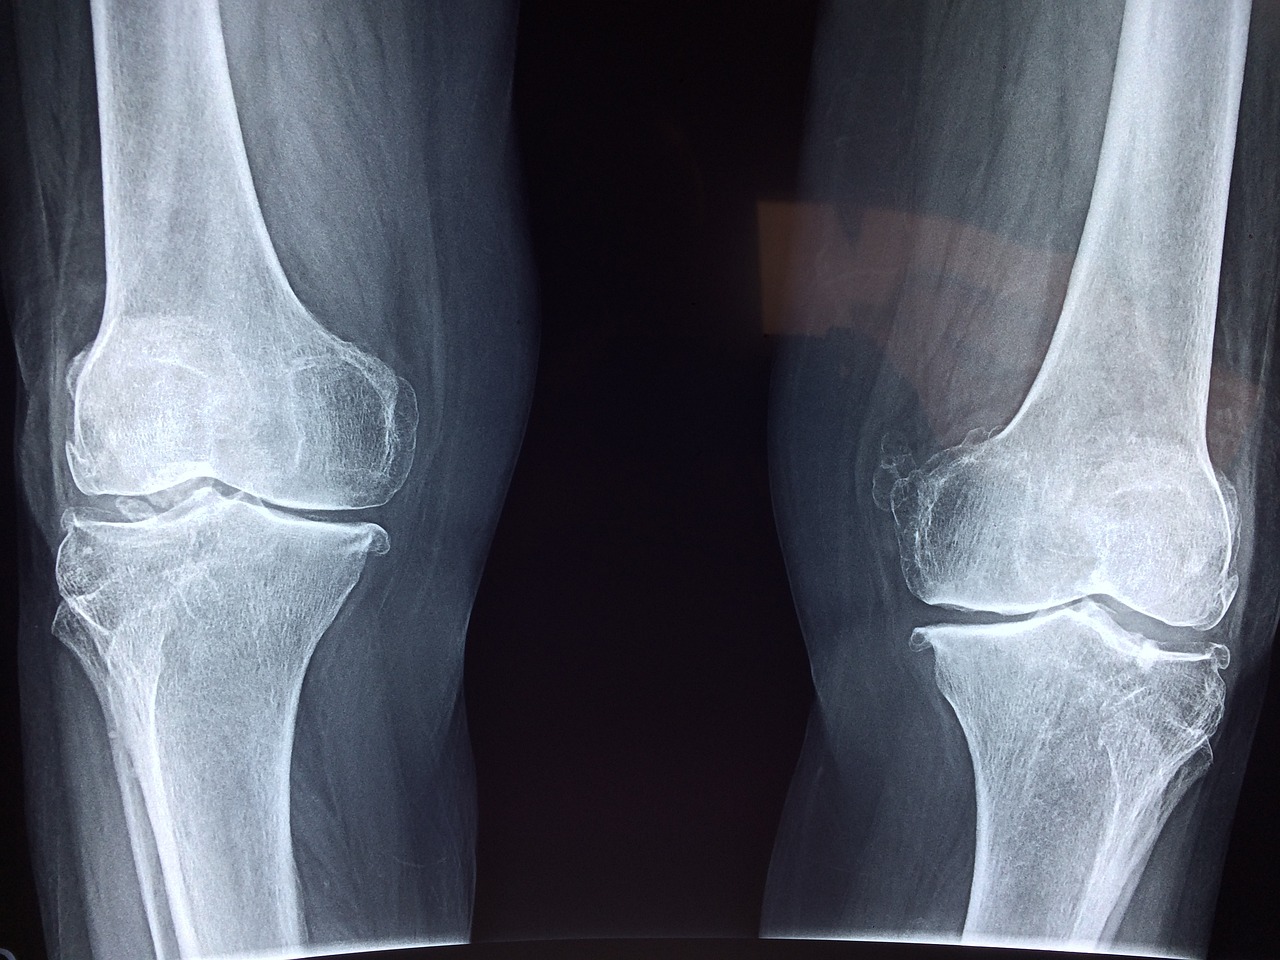

1) 영상 검사:

- X-ray : 초기 단계에서는 X-ray에서 별다른 이상이 보이지 않을 수 있지만, 진행된 경우에는 뼈의 변형이나 손상을 확인할 수 있습니다.

- MRI : 골괴사증 진단에서 가장 유용한 검사로, 뼈의 내부 구조와 혈류 상태를 자세히 보여줍니다. 초기 단계에서도 변화를 감지할 수 있습니다.

- CT 스캔 : 더 정밀한 뼈의 구조를 확인하기 위해 사용될 수 있으며, 뼈의 손상 정도를 평가하는 데 도움이 됩니다.